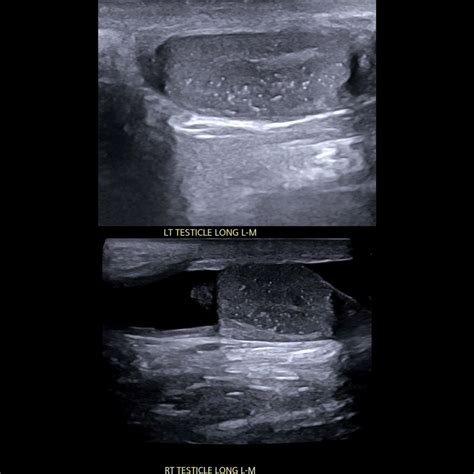

Testicular microlithiasis is defined by the presence of multiple, tiny calcium deposits scattered throughout the seminiferous tubules of the testes. When observed via high-frequency ultrasound, these deposits appear as multiple small, “bright” echogenic foci. They are typically asymptomatic, meaning they do not cause pain, swelling, or changes in fertility on their own. The condition is often classified based on the number of these spots visible per ultrasound image.

The Role of Scrotal Ultrasound

The ultrasound remains the gold standard for diagnosing microlithiasis in testis. Because it uses sound waves rather than ionizing radiation, it is a safe and highly effective diagnostic tool. During the procedure, the radiologist looks for the characteristic “starry sky” appearance, which signifies the presence of calcium deposits. It is important to emphasize that an ultrasound is highly sensitive, meaning it can detect even the smallest calcifications that have no clinical significance.